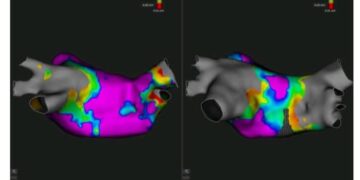

نجح الفريق الطبي بالمستشفى الجامعي سهلول، يوم الأربعاء 4 فيفري 2025، في إجراء أول عملية لاستئصال اضطرابات نبضات القلب باستخدام نظام “Rythmia” المتطور، الذي يتيح تشخيصًا دقيقًا وعلاجًا موجّهًا لهذه الحالات المعقدة.

واجرى هذه العملية، الأستاذ إلياس النفاتي، رئيس قسم جراحة القلب والشرايين، والأستاذ وليد نعيجة، رئيس قسم التخدير والإنعاش، وفق بلاغ صادر عن وزارة الصحة، اليوم الخميس 6 فيفري 2025.